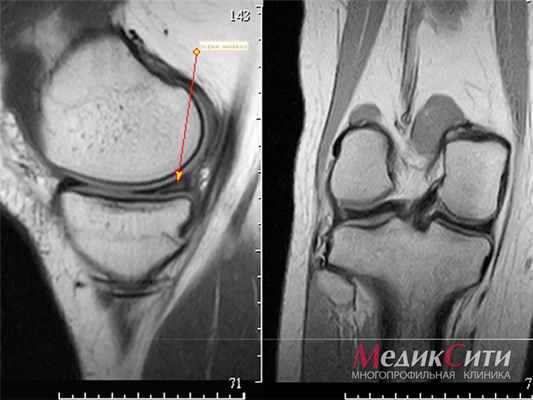

- данные УЗИ либо МРТ суставов (если это необходимо врачу на ранней стадии заболевания);

- ренгенография суставов.

I стадия. Редко может ощущаться некоторая скованность и дискомфорт. Как правило, диагностируется случайным образом. При УЗИ- уплотнение и утолщение околосуставных мягких тканей, воспалительная жидкость в суставе (синовит).

II стадия. Воспаление прогрессирует, оболочка сустава истончается, возникают болезненные трения между головкой кости и суставной впадиной. Появляется отечность, покраснение в области поражения и местное повышение температуры. При рентгенографии - сужение суставной щели, нарастанием околосуставного остеопороза.